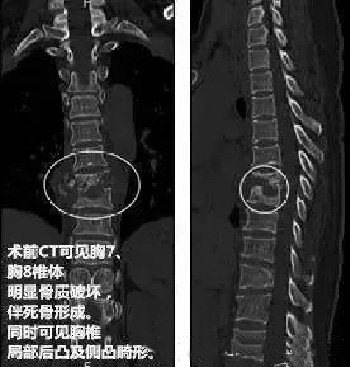

接诊后,医生给陈女士做了胸片检查,检查发现陈女士脊柱有一大块阴影,有可能是骨结核。通过 CT 检查发现,陈女士的胸 7、胸 8 椎体有一个大空洞, 就像被蛀虫咬了一样,整个椎体都塌了下来,导致脊椎的棘突凸起。这就是她背上有一个明显凸起的原因所在。

经过进一步检查发现,导致陈女士脊柱被掏空的原因竟然是 " 结核 " ——一种经常发生在肺部的传染病。陈女士中招的却是脊柱,也就是所谓的 " 骨结核 "。肺结核一般有咳嗽、咳痰、咯血、胸痛等症状,而骨结核症状则比较隐匿。由于早期未发现时结核病,结核细菌在陈女士体内不断破坏,骨关节和脊椎骨质被侵蚀,最终就像骨头被掏空一样。

" 随着疾病的进展,关节活动逐渐受限,最终出现了成角后凸畸形。" 刘少喻教授介绍说," 如果疾病进一步发展,一旦脊髓受到压迫、损伤或牵拉,就有可能导致瘫痪!"